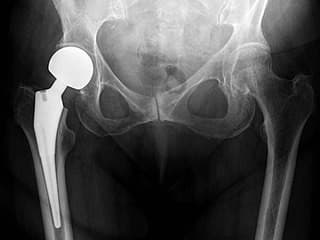

Total Hip Arthroplasty – үеийг бүтэн солих мэс засал

Хугарал засах мэс засал image9

УНТЭ-т хийгдсэн мэс заслын зураг